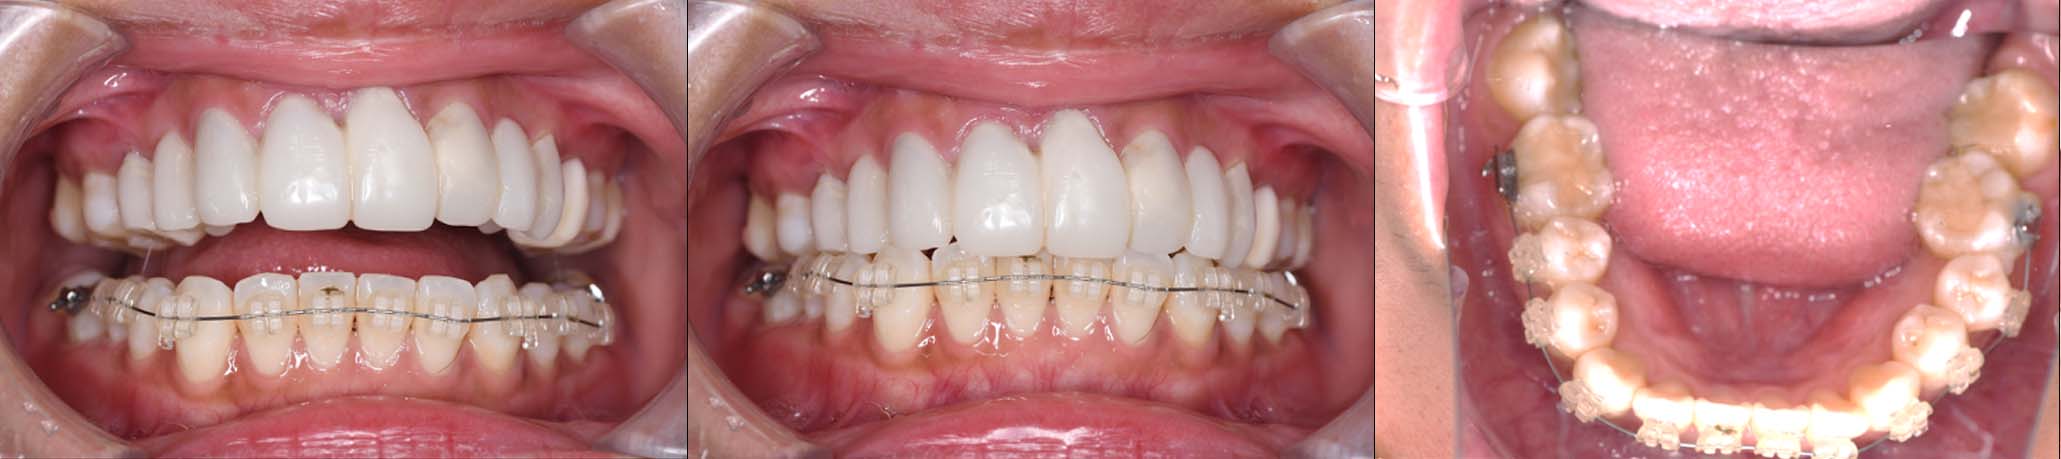

2024年 10月 下顎MTM開始

2024年 10月10日

10月21日

11月7日

11月28日

12月16日

12月23日

1月9日

1月30日

2月20日

3月13日

4月24日

9月25日